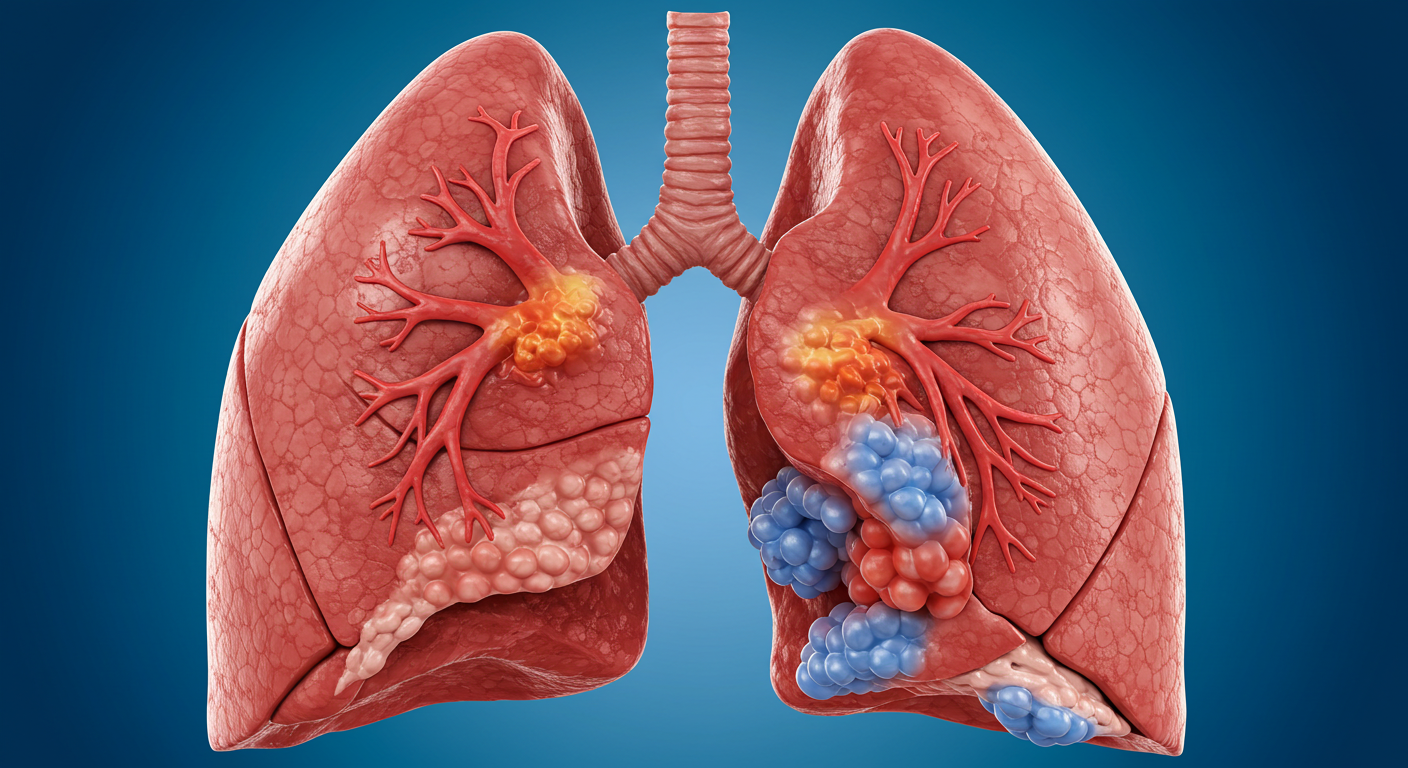

폐렴은 흔히 세균이나 바이러스, 곰팡이 등에 감염됨으로써 폐에 염증이 생기는 질환이다. 대부분 고령자와 면역력이 약한 사람에게 생길 수 있으며, 조기에 발견하지 않는다면 다소 치명적일 수 있다. 의심이 가는 증상들이 나타난다면, 초기 증상을 빠르게 인지하고 원인을 파악해 적절한 치료와 회복에 집중하는 것이 중요하다. 또한 회복을 돕는 음식을 섭취하고 이에 따른 자연 요법도 같이 병행한다면 폐 기능 회복을 빨리 가져올 수 있다.

폐렴은 특히 겨울철이나 환절기에 자주 발병한다. 그 대표적인 증상은 기침이나 가래, 흉통, 고열, 오한, 호흡곤란 등으로 나타나며, 증상이 심할 경우에는 입원을 해서 치료를 받아야 할 수도 있다. 이중에서도 폐포에 염증이 생기면서 산소와 이산화탄소 교환이 어려워지며, 피로와 무기력감을 동반할 수 있다는 점이 특징이다. 특히 65세 이상의 고령자나 면역력이 아직 발달하지 않은 유아, 만성질환자, 면역 저하자에게는 폐렴이 빠르게 악화될 수 있으므로 조기에 발견하여 각별한 주의가 필요하다.